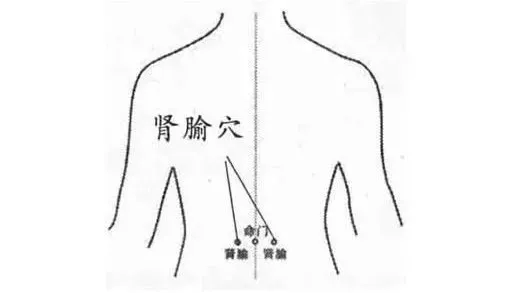

- 中医认为,腰眼居"带脉",是肾脏所在部位.

- 肾, 喜温恶寒,常按摩腰眼,可 温煦肾阳,畅达气血.

- 肾俞穴在背部腰眼处,即第二腰椎棘突往上两椎体,旁开1.5寸位置.

- 肾俞穴(两边腰眼)